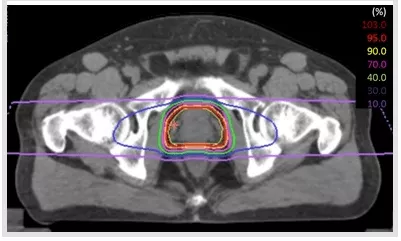

但是傳統(tǒng)的光子放療會(huì)導(dǎo)致直腸和膀胱不良事件的產(chǎn)生,不利于前列腺癌患者生活質(zhì)量的提升。與傳統(tǒng)的光子放療不同,質(zhì)子治療及重離子治療這兩種新興的放療手段在人體內(nèi)會(huì)產(chǎn)生“布拉格峰效應(yīng)”,簡單說就是進(jìn)入人體時(shí)能量小,達(dá)到腫瘤處能量突然暴增,因此對(duì)正常組織損傷非常小。相比傳統(tǒng)的光子放療,質(zhì)子重離子治療前列腺癌的效果更加顯著,且減少了膀胱、直腸和陰莖球的輻射劑量,副作用更低。

▲重離子治療前列腺癌|圖源:日本QST醫(yī)院